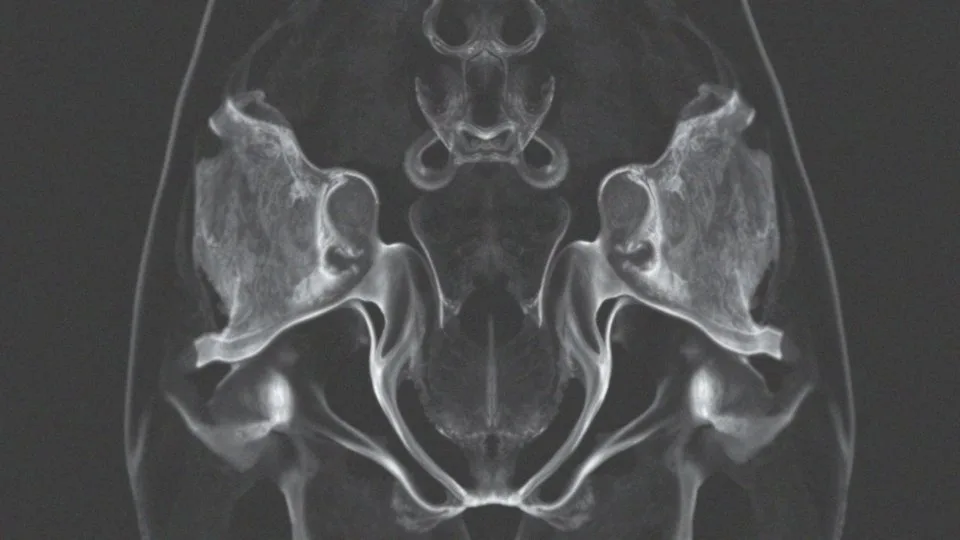

Rezonans magnetyczny miednicy, znany również jako MR miednicy, to innowacyjna technika obrazowania, która pozwala na szczegółową analizę narządów w obrębie miednicy mniejszej. Dzięki zastosowaniu zaawansowanej technologii obrazowania wielopłaszczyznowego, badanie to zapewnia imponującą rozdzielczość oraz kontrast, co umożliwia dostrzeganie nawet najdrobniejszych zmian patologicznych. Koncentruje się głównie na elementach układu moczowo-płciowego, takich jak:

Jakie narządy ocenia rezonans miednicy mniejszej?

Rezonans miednicy mniejszej jest niezwykle istotnym badaniem, które ocenia szereg kluczowych narządów. U kobiet koncentruje się na:

- pęcherzu moczowym,

- macicy,

- jajnikach,

- jajowodach.

Natomiast w przypadku mężczyzn zwraca uwagę na:

- prostatę,

- pęcherzyki nasienne.

Badanie obejmuje również analizę:

- odbytnicy,

- węzłów chłonnych,

- struktur kostnych miednicy.